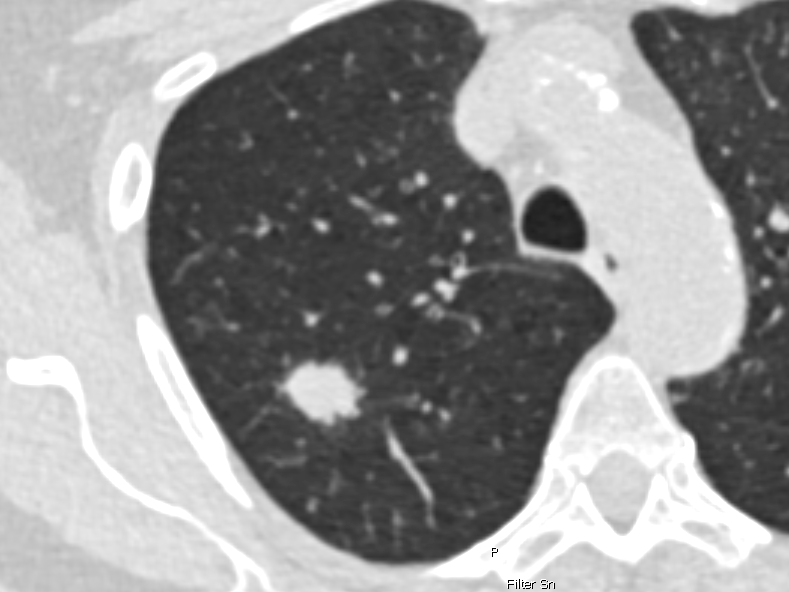

CT-Aufnahme einer Lunge.

Niedrigdosis-CT-Aufnahme der Lunge einer 69-jährigen Raucherin. Die weiße rundliche Fläche im Lungengewebe deutet auf Lungenkrebs im Frühstadium hin. In diesem Stadium kann Lungenkrebs noch gut behandelt werden. Copyright: Charité/ Jens Vogel-Claussen